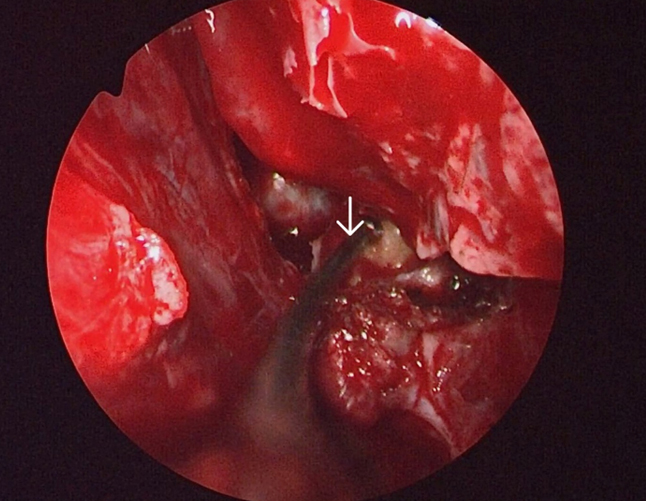

The surgery was performed under general anaesthesia by the first author. Nasal endoscopic examination after administering general anaesthesia showed watery discharge from the region of the left cribriform plate (figure3 B) and the left spheno-ethmoidal recess (figure 4). The surgery proceeded with left partial middle turbinectomy and widening of the sphenoid ostium on the left side. This was followed by left uncinectomy, middle meatal antrostomy, left anterior ethmoidectomy an removal of basal lamella and posterior ethmoidectomy. This was followed by clear delineation of the leak in the left cribriform plate and a wide sphenoidotomy (figure 5). The edematous sphenoid sinus mucosa was removed and the meningoencephalocele was seen in the left lateral recess above the vidian-rotundum line. The sphenoplalatine foramen was identified and the sphenopalatine artery cauterized. The medial aspect of the posterior wall of left maxillary sinus was removed partially. The upper part of the pterygoid process was drilled out and widened laterally exposing the antero-medial temporal lobe and the meningoencephalocele (figure 6) and the continuous csf leak leak identified.

Figure 6. Arrow showing the meningoencephalocele in the left lateral recess of sphenoid with csf leak through the defect